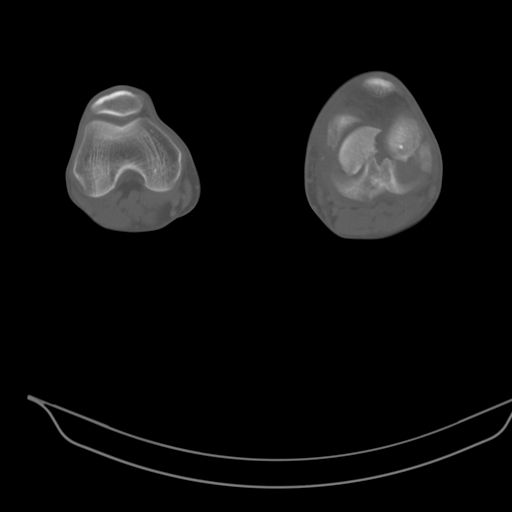

Качественные только исходные рентгенограммы (вышлю или завтра или в понедельник). Все последующие рентгенисследования были малоинформативны

(в т.ч. и последние снимки). КТ-исследование делалось 3 или 4 дня назад...

This is a coronal split in the femoral condyle and is a rare injury. Please see attachment for ORIF result

CT shows major bony fragments which are markedly rotated .With this amount of bony damage,you probably should attempt to get reasonably loooking knee with ORIF and thn if he needs a TKR due to pain a few years from now, then tleast you have something looking like a knee that you can replace rather than having to use revision knee for a primary TKR now. 4 weeks is not too long .what is the condition of soft tissues?

При внутрисуcтавных переломах трехмерные (3D) изображения, кроме красивого снимка, не дают полную информацию о состоянии отломков, самыми информативными являются корональные срезы на КТ и обычная длинная ренгенограмма конечности для сравнения оси конечности.

Фронтальные внутрисуставные переломы мыщельков бедра, так называемые Hoffa fracture, не частые, но встречающиеся переломы, в основном они связаны с травмой высокой энергией.

В вашем случае доступ будет медиальный, сопоставить развернутый медиальный мыщелок и фиксацию надо произвести в передне-заднем

направлении шурупами 4.5 мм в диаметре, углубив головку шурупов под хрящ, а поперечную фиксацию - межмыщелковыми шурупами. Желательно применить шурупы 6.3 мм в диаметре. Дополнительная Buttress technique пластина предотвратит перелом от скольжения.